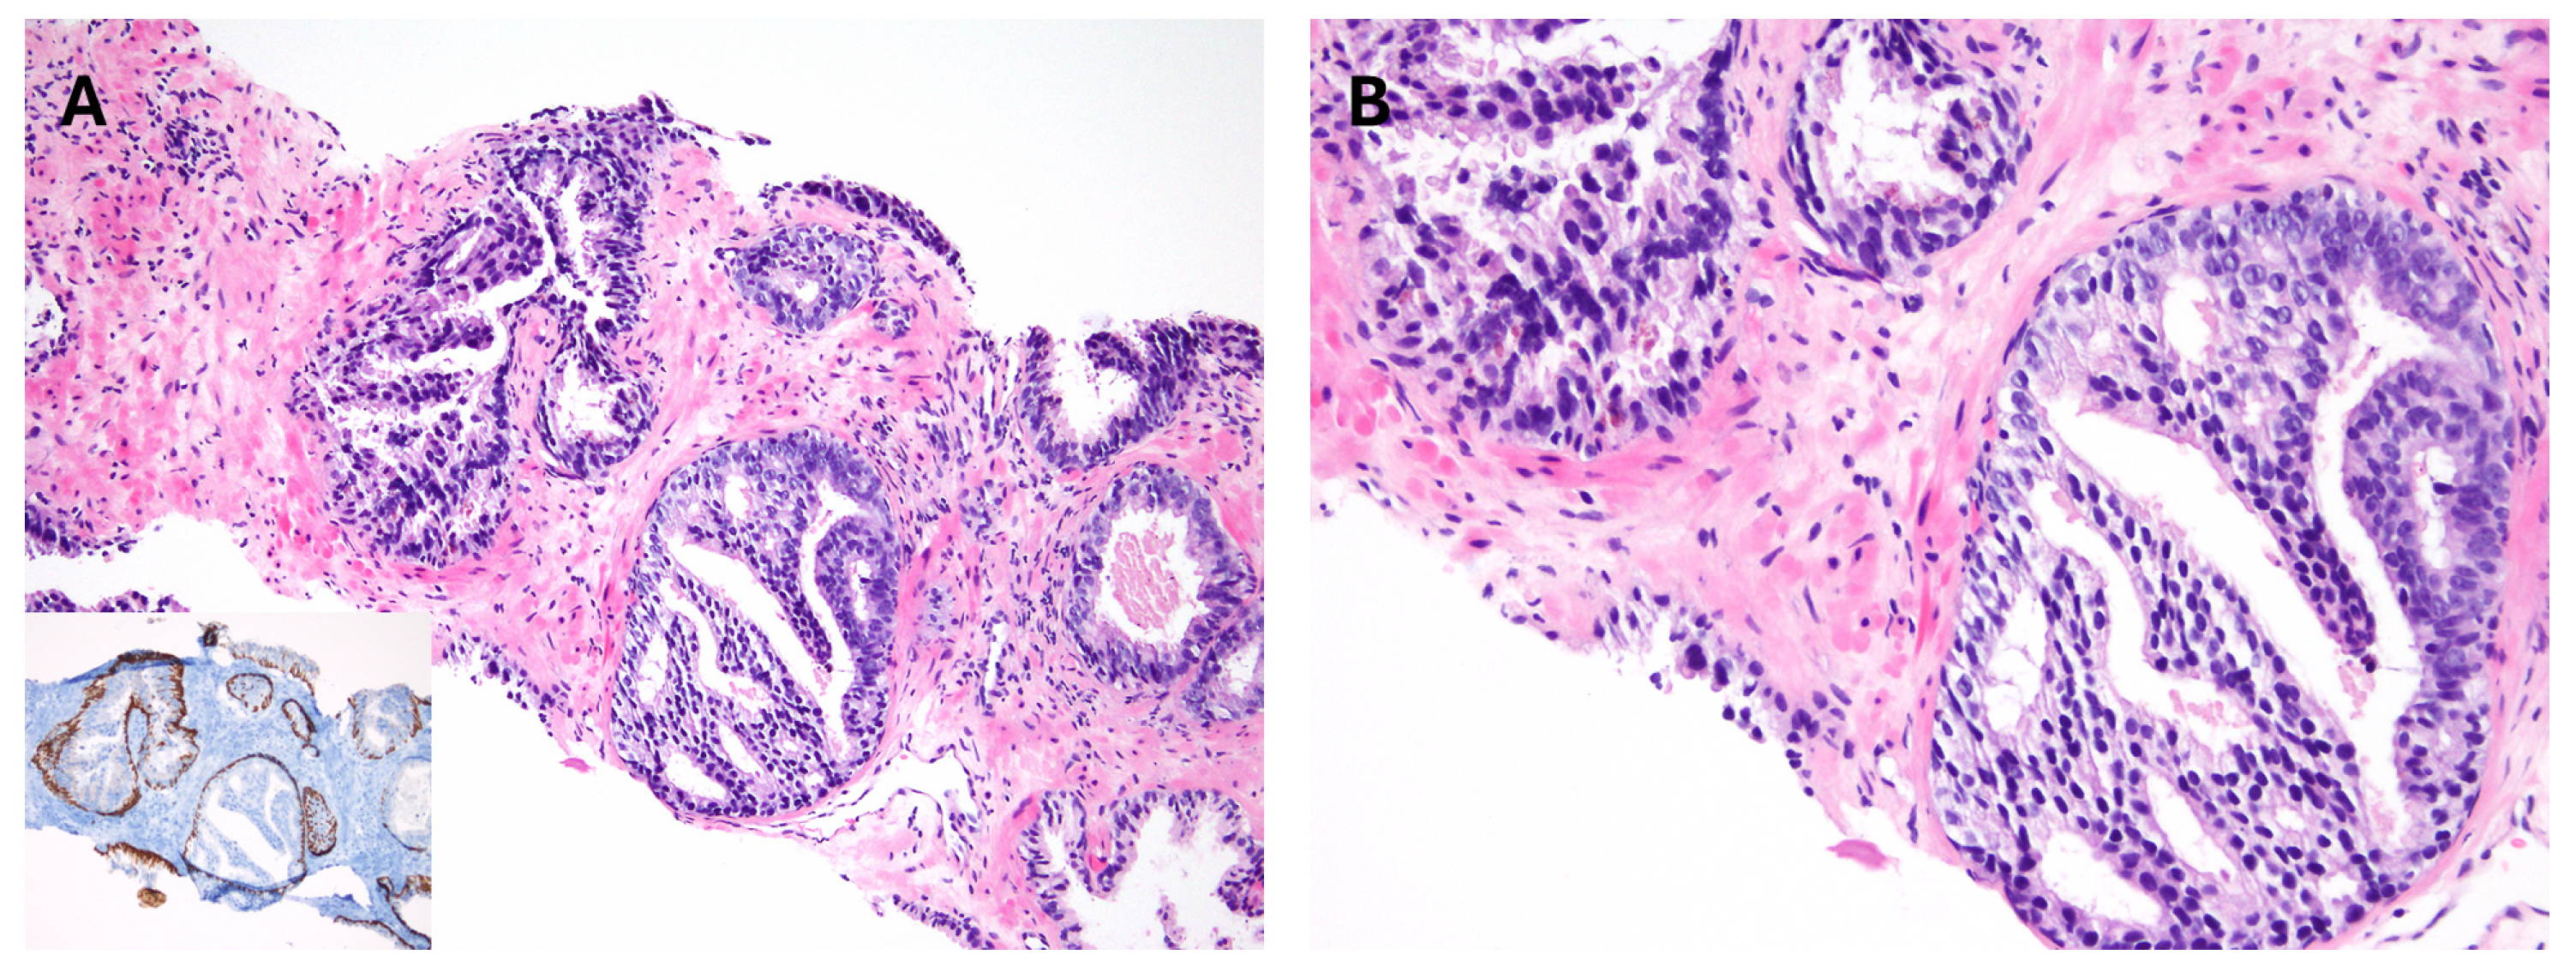

Figure 7.

(A) Intraductal carcinoma in biopsy with (B) basal cell marker expression. (C) Intraductal carcinoma with basal cells discernible in H&E (arrow). (D) Non-cribriform Intraductal carcinoma with markedly pleomorphic nucleoli.